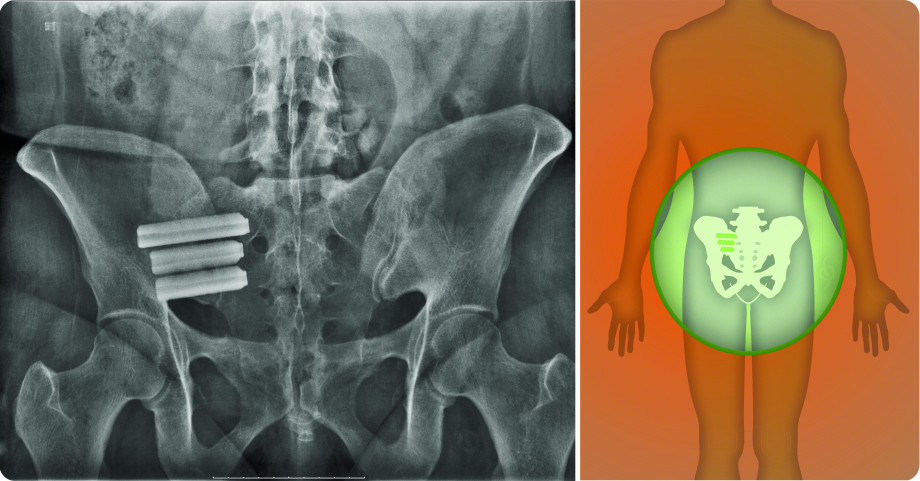

SI Joint Fusion with the iFuse Implant System®

The iFuse Implant System is designed to provide stabilization and fusion for certain Si joint disorders. This is accomplished by inserting triangular-shaped titanium implants across the sacroiliac joint to maximize post-surgical stability and weight-bearing capacity. The procedure is done through a small incision and takes about an hour. Multiple published studies on iFuse have documented procedure safety and effectiveness.

The iFuse Implant System® is intended for sacroiliac fusion for conditions including sacroiliac joint dysfunction that is a direct result of sacroiliac joint disruption and degenerative sacroiliitis. This includes conditions whose symptoms began during pregnancy or in the peripartum period and have persisted postpartum for more than six months. Clinical studies have demonstrated that treatment with the iFuse Implant System improved pain, patient function, and quality of life at 12 months post-implantation. There are potential risks associated with the iFuse Implant System. It may not be appropriate for all patients and all patients may not benefit. For more information about the risks, visit www.si-bone.com/risks.